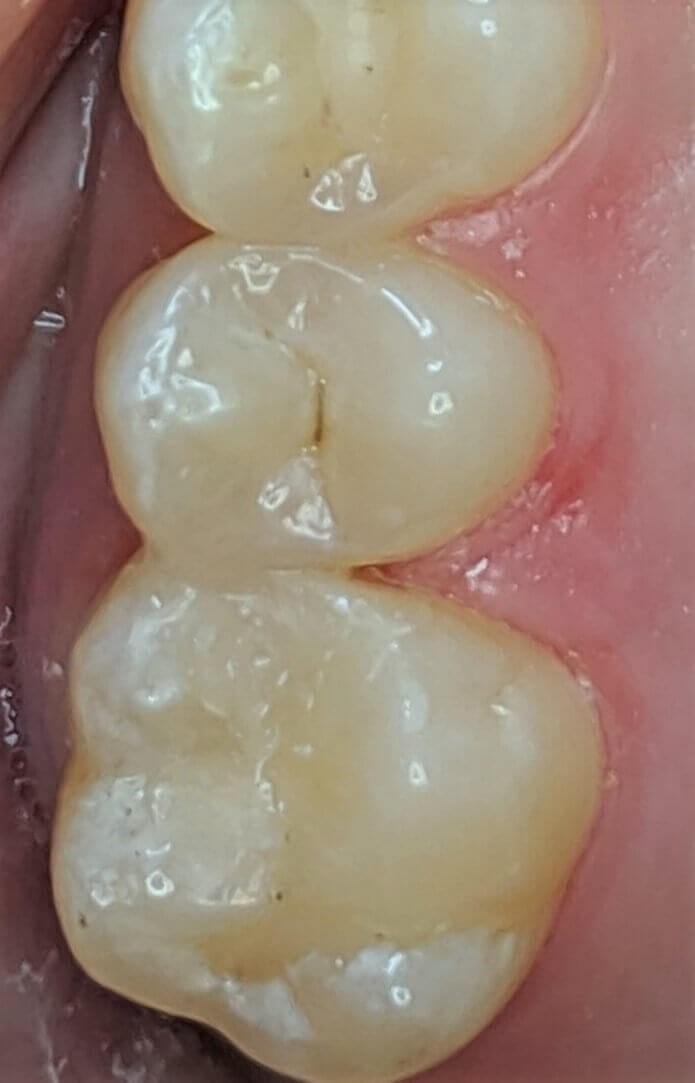

Cavities, one of the most common dental problems, are created when bacteria erode your dental enamel. In the past, dental cavities were filled with a material called amalgam, which is a mixture of different metals, such as silver or mercury. Now we know that amalgam fillings do not bond well with the teeth and the mercury is dangerous to your health. At Luminous Dental Studio in Frisco, TX, dentist Dr. Nam Kim offers tooth-colored fillings made from a composite resin to fill and protect cavities. Dr. Nam Kim or Dr. Minho Chang can also remove old metal fillings and replace them with tooth-colored fillings for a better-looking treatment of cavities. The other benefits of tooth-colored resin filling include:

Luminous Dental Studio is a mercury-free dental practice. Dr. Kim and Dr. Chang want you to have teeth that have a natural-looking aesthetic. The composite resin we prepare today is effective stain resistance, longer-lasting color, translucency, and take a long time to wear down. Find out more at your consultation at our Frisco, TX practice.

Tooth-colored fillings often fill in the decay in the enamel after it has been cleaned. Composite resin is a versatile material that can be used to treat other problems with your teeth, including cracks or enamel that has been worn down by teeth grinding (bruxism). Since the composite resin is colored to match your natural teeth, tooth-colored fillings can be used on both the front and back teeth for a seamless appearance. If you have metal fillings, talk to Dr. Kim or Dr. Chang about having them removed and replaced with tooth-colored fillings.